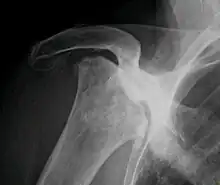

Necrose avascular, também é conhecida como osteonecrose, necrose asséptica ou necrose isquêmica do osso, é uma doença causada pela perda temporária ou permanente da irrigação de sangue aos ossos. A morte do tecido ósseo causa seu colapso resultando em dor e deficiência.

Inicialmente pode ser diagnosticado por ressonância magnética, aparecendo como normal em um Raio-X a menos que já seja severa.[1]